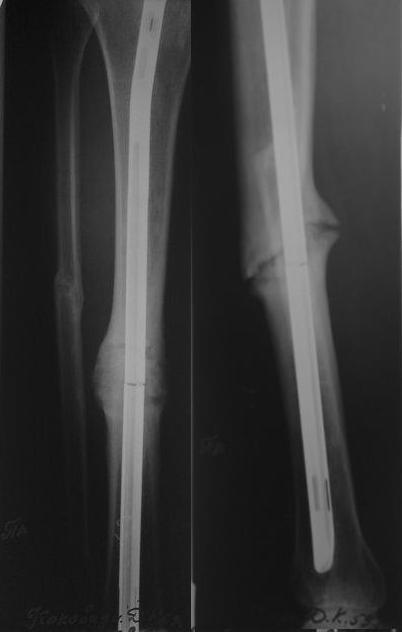

Уважаемые коллеги! У пациента 50-ти лет ложный сустав голени, перелом интрамедуллярного штифта. Перелому около 2 лет, ходить с полной нагрузкой начал через 3 мес. после операции. Боли при ходьбе почувствовал около 2 мес. назад. На данный момент ходит с полной нагрузкой без посторонней опоры. Среди коллег развернулась дискуссия по поводу способа оперативного лечения: -удаление штифта с перештифтовыванием блокированным штифтом с рассверливанием и остеотомией м\б кости -стабилизация зоны ложного сустава по медиальной поверхности LCP-пластиной с декортикацией или без -удаление штифта или без и синтез в АВФ с декотрикацией или без и остеотомией м\б кости

уважаемый коллега! Здесь имеется типичный тугой ложный сустав б/берцовой кости. У нас бы удалили старый стержень, реостеосинтез более толстым стержнем с рассверливанием с блокированием в динамическом варианте. Проблема будет с удалением дистального отломка стержня. Здесь на форуме это вопрос уже рассматривался неоднократно. Поищите по поисковику.Вот здесь, кажется http://weborto.net/forum/1164105478/, http://weborto.net/forum/1192794837

Сросшаяся малоберцовая как распорка привела к образованию ложного сустава. В таких случаях удаляем сломанный штифт и проводим стимуляцию ложного сустава рассверливанием. Рассверливание канала создает стимуляцию на месте ложного сустава, и динамический вариант блокировки штифта с большим диаметром создаст стабильность. Ранняя нагрузка после остеотомии малоберцовой приведет к сращению ложного сустава.